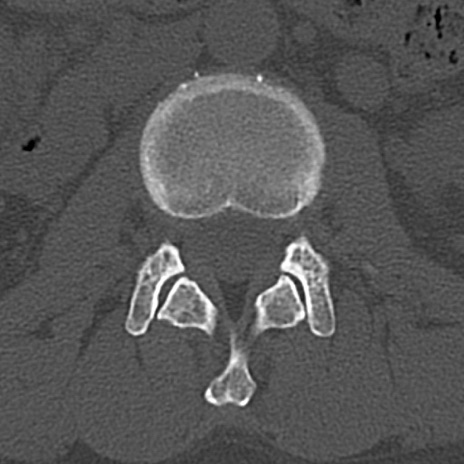

腰椎CT

横断像と矢状断像